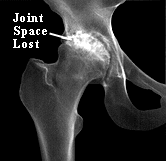

An X-Ray and Illustration Showing an Arthritic Hip Joint

Osteoarthritis mainly damages the joint cartilage, but there is often some inflammation as well. It usually affects only one or two major joints (usually in the legs). It does not affect the internal organs. The cause of hip osteoarthritis is not known. It is thought to be simply a process of wear and tear in most cases. Some conditions may predispose the hip to osteoarthritis, for example, a previous fracture that involved the joint. Growth abnormalities of the hip (such as a shallow socket) may lead to premature arthritis. Some childhood hip problems later cause hip arthritis (for example, a type of childhood hip fracture known as a Slipped Epiphysis; also Legg-Pertheís Disease). In osteoarthritis of the hip the cartilage cushion is either thinner than normal (leaving bare spots on the bone), or completely absent. Bare bone on the head of the femur grinding against the bone of the pelvic socket causes mechanical pain. Fragments of cartilage floating in the joint may cause inflammation in the joint lining, and this is a second source of pain. X-rays show the ìjoint spaceî to be narrowed and irregular in outline. There is no blood test for osteoarthritis.